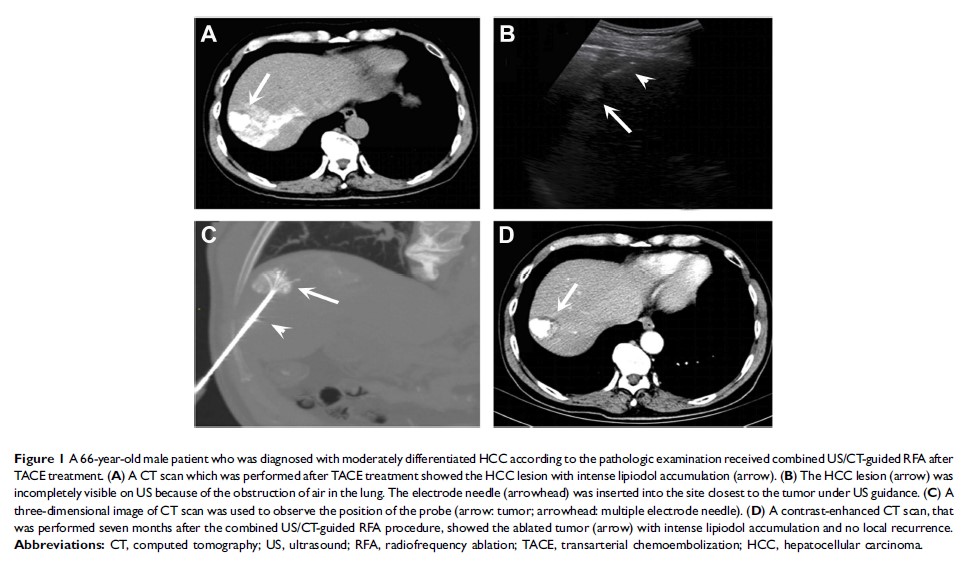

在实施经肝动脉化疗栓塞术后,结合超声/计算机断层扫描引导的经皮射频消融术治疗肝脏膈顶部肿瘤